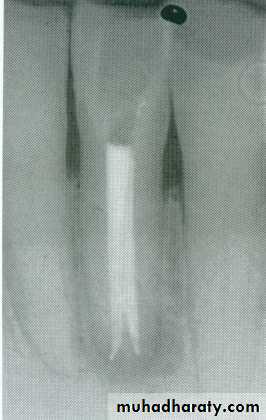

Single root-type I canal configurationCanal shape: Simple, large, conical, tapered toward the apex and the Pulp chamber gradually merging into the root canal.Slightly triangular or oval in shape at the cervical area of the root and tend to be round at the apical portion.

Apical foramen exists short of the apex to the labial direction.Average length:22mmIf the lingual shoulder not cut during access opening, it will lead to obstructed line during canal preparation.